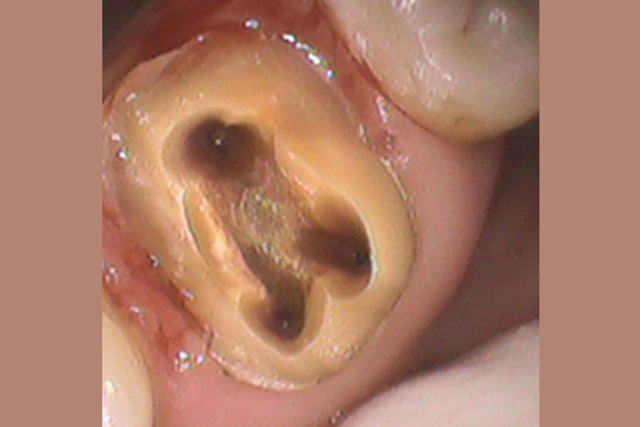

②銀歯を被せた歯がまた虫歯を再発する

銀歯と歯は歯科用の接着材でペタンとくっつけています。

しかし、正確にいうとぴったりとくっついているわけではありません。

封鎖性が非常に弱いため隙間があるのです。

銀歯を入れる際に歯との隙間を接着材で埋め、

くっつけているだけ、です。

隙間があるので隙間からは細菌は侵入し放題です。

お口の中には目に見えない何百億の細菌が存在します。

侵入し放題の虫歯菌により、せっかく治療した歯の中に虫歯が再発します。

銀歯のセメントも劣化してくるので、古い銀歯の中で、元々の歯が真っ黒になっていたといったこともよくあります。